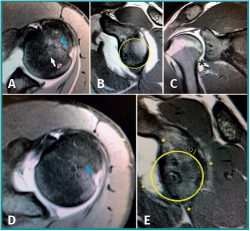

Figura 2. Resonancia magnética de un paciente de 19 años con inestabilidad glenohumeral con lesión del ligamento glenohumeral inferior asociada (asterisco). A y B: cortes axial y sagital preoperatorios. Se aprecia integridad de la glena y lesión de Hill-Sachs (flecha). La lesión ligamentosa fue pasada por alto y se realizó únicamente reparación artroscópica de la lesión de Bankart. A los 6 meses de la operación el paciente sufre un nuevo episodio de luxación. D y E: cortes axial y sagital tomados en resonancia posterior al fracaso de la intervención de Bankart. Se aprecia aumento de tamaño de la lesión de Hill-Sachs e importante defecto en la glena anterior respecto a la resonancia preoperatoria.